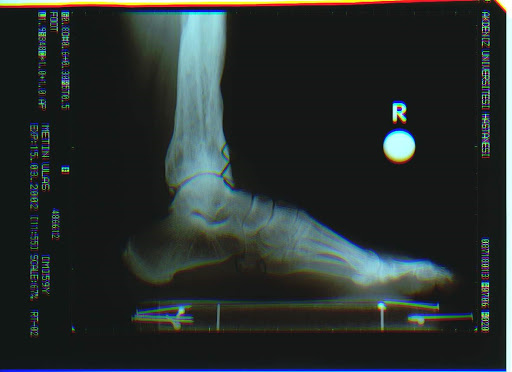

Talus Avasküler nekrozu (AVN)

Kalça bölgesinde olduğu gibi kemiği besleyen damarların tıkanması sonucu kemik ölümü ve üstündeki kıkırdağın bozulnasını içeren bir tablodur. Talus ayakla baldır arasında menteşe görevi gördüğü için oldukça ciddi sorunlara yol açabilir.